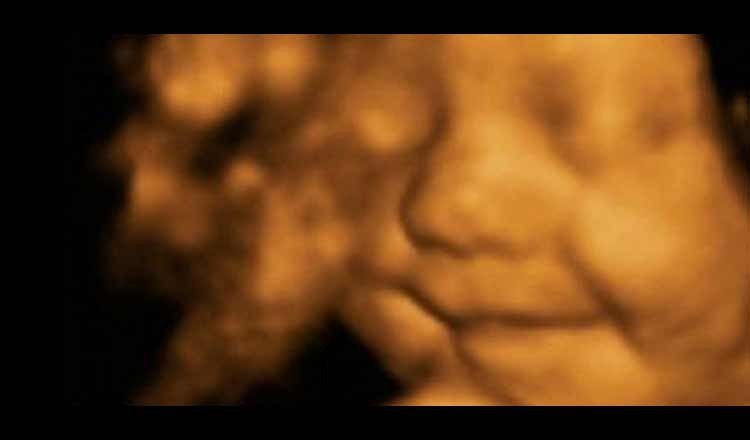

Ultrasonido captura bebé sonriente en el vientre – una imagen de ultrasonido muestra un bebé de siete meses que sonríe en el útero está causando asombro, ya que capta claramente la sonrisa feliz del niño.

La ecografía fue tomada cuando la madre de Amy Cregg, de 24 años, fue a Babybond Ultrasound Direct en Burnley para una exploración 4D a las 31 semanas. La forma más popular de ultrasonido usa fotografías tomadas desde un número de ángulos para producir un muy claro video del niño en la pantalla.

Cregg dijo a los periodistas que cuando vio la imagen de su hijo sonriendo de oreja a oreja, ella se sorprendió.

«[Nosotros] estábamos absolutamente impactados», dijo, refiriéndose a su novio – Clegg es una madre soltera – «Incluso la gente que hizo mi exploración se sorprendió.»

«Nuestra ecografista que escanea Amy y su precioso bebé estaba abrumada al ver a su bebé sonriente en toda la exploración», le dijeron a The Telegraph. «Creo que podemos decir con seguridad que el bebé de Amy ha sido el bebé más sonriente que hemos visto nunca.»